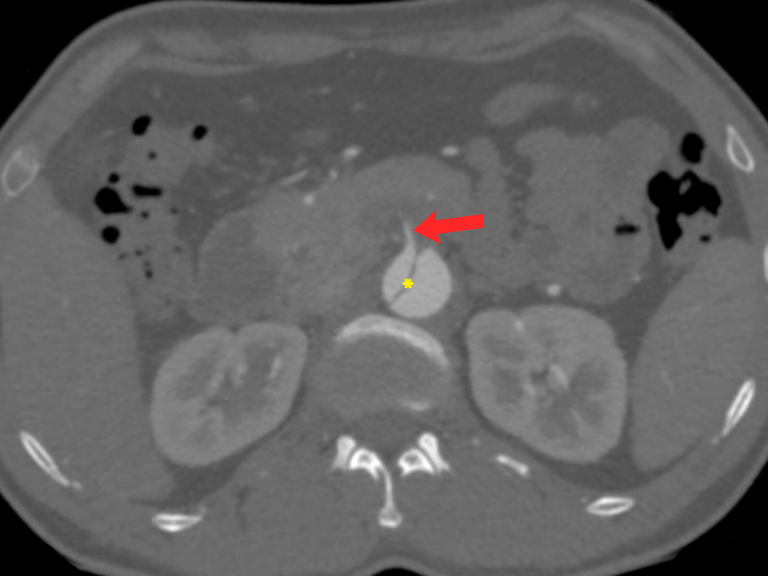

Figure 13 Axial CT angiography image in the delayed phase shows an aortic aneurysm (white asterisk) in the descending aorta with displaced intimal calcifications and a break in the rim of calcifications in its lateral aspect (red arrow). Focal discontinuity of intimal calcification is a predictor of aortic aneurysm instability.